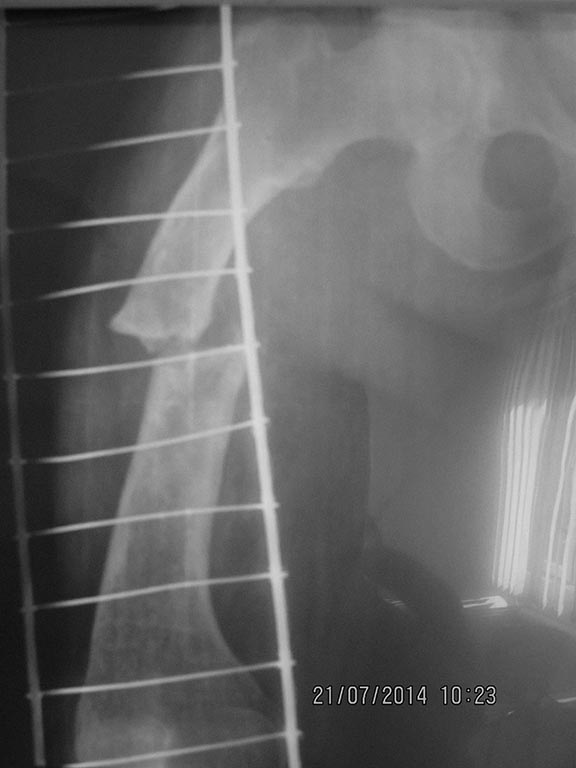

[Ortho] перелом бедра с исходной деформацией

Имя     : IMG_2890.jpg

Тип     : image/jpeg

Размер  : 53053 байтов

Url     : http://weborto.net:8080/pipermail/ortho/attachments/20140721/a09be377/attachment-0007.jpg